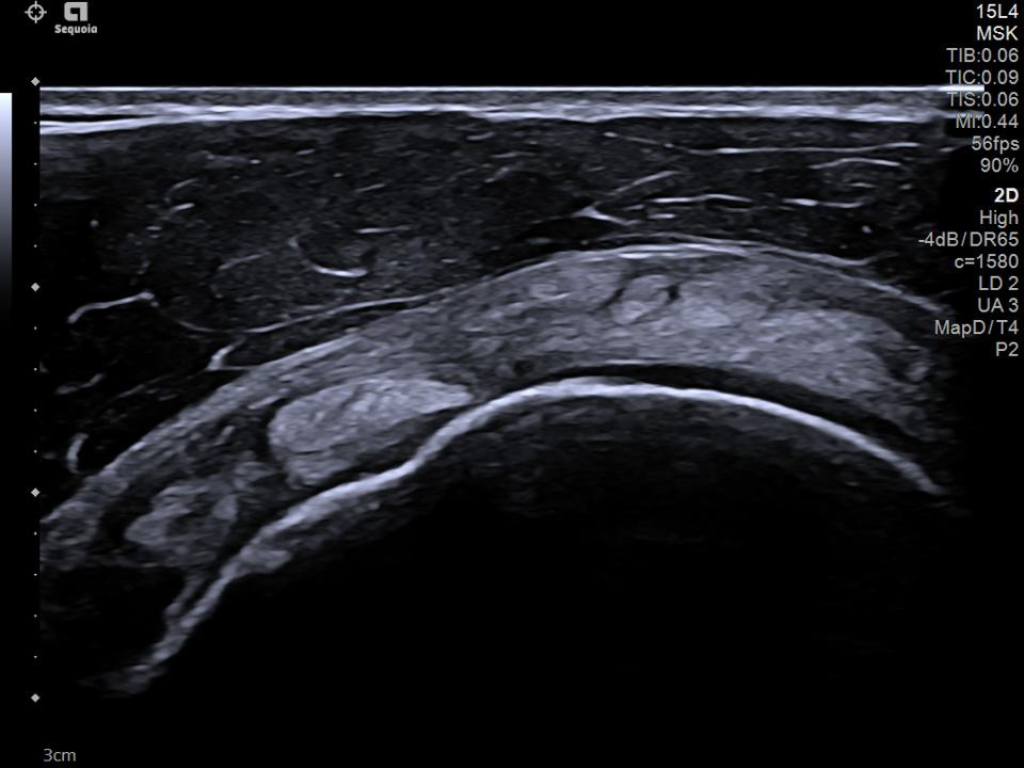

The latest updates on ACUSON Sequoia use the power of groundbreaking AI for abdominal cases, includes advanced breast visualization to deliver new levels of image quality confidence, and tackles the toughest challenges in musculoskeletal imaging, all while saving your team from needless strain and pain.

ACUSON Sequoia’s InFocus imaging architecture eliminates the need for conventional focal zones to create a fully focused image faster than conventional systems. Our InFocus technology applies to all imaging transducers and exam types giving you consistent imaging across clinical segments. Some of the benefits are:

- High resolution imaging at high frame rates